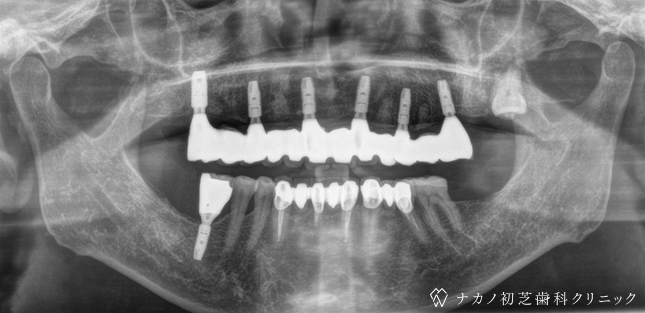

インプラント・7本 (70代男性)

AFTER

BEFORE

年齢 70代男性

治療内容 インプラント治療7本(骨造成の併用)

インプラント治療とは、歯を抜いた所にチタン製の人工歯根を埋入し、その上に歯を入れる方法です。骨を増やすことで、より審美的に治療が出来ました。費用 1本 400,000円(税込 440,000円)

リスク・副作用

腫れ・疼痛・違和感を感じるなどの症状を生じることがあります。